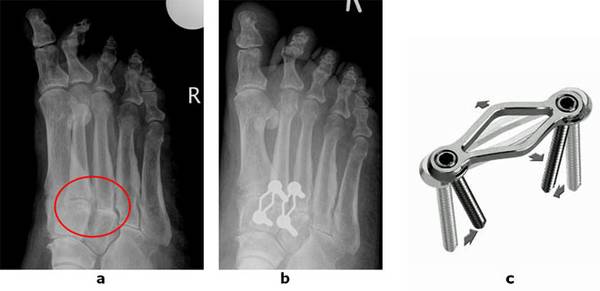

Abb.1 a: Arthrose zwischen Mittelfuß und Vorfuß (TMT Gelenk) b: Fusion des Gelenkes mit einer Spezialplatte

c: Die verwendete Stabilisierung erlaubt einen minimalinvasiven Zugang. Das Klammer/Schraubensystem erlaubt eine maximale Kompression auf den Fusionsspalt und verbessert die Heilungsrate.